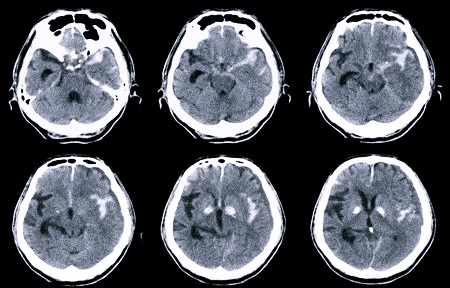

Томография головного мозга (КТ, компьютерная томография) – это исследование, при котором используются рентгеновские лучи, создающие изображения человеческого тела. КТ-изображения имеют большое преимущество перед простыми снимками, получаемыми при других методах визуализации тканей.

КТ головы – это возможность быстрого и качественного получения большого объема информации о состоянии мозга больного, что в конечном итоге может значительно повлиять на лечение. Субмиллиметровые срезы – это необходимое условие для идеальной трехмерной обработки полученных данных, являющейся неотъемлемой частью оценки состояния пациента при базовом обследовании, создающем пространственное изображение органов и связь патологических процессов.

Что показывает КТ головного мозга? РКТ полезна при диагностике в случае травмы (ушиба) головы, поражения мозга. Это обследование может исключить или подтвердить воспалительные процессы, которые невозможно обнаружить иначе. Оно играет важную роль в диагностике рака. Также КТ показано после инфаркта головного мозга (инсульта) и кровотечения, для исследования мозговых кровеносных сосудов (ангиография).

КТ может выявлять патологии в областях, которые невозможно оценить на обычном снимке. Этот метод определяет диагноз раньше и точнее, что позволяет врачу своевременно начать лечение, следовательно, сократить время заболевания.

Метод позволяет легко обнаружить даже небольшие воспаления, опухоли, метастазы, кровотечения и их точное положение. Современная компьютерная томография может отображать трехмерные изображения в очень короткие сроки. С использованием КТ также может быть выполнено терапевтическое вмешательство (пункция, биопсия, дренаж). Для некоторых исследований необходимо применение контрастного вещества, требующего предварительной подготовки пациента.